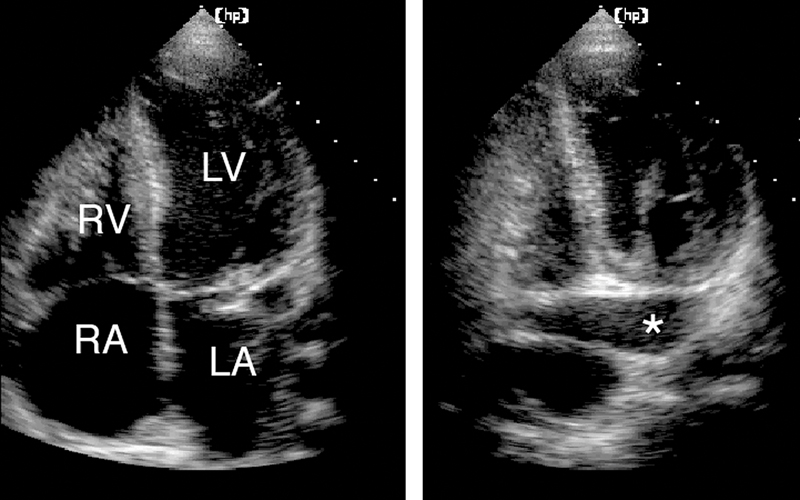

فحوصات تشخيصية لبعض امراض القلب والشرايين التاجية